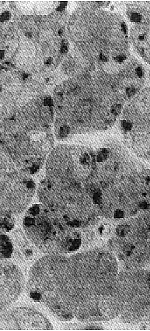

腺泡大致呈圆形,腺泡细胞呈锥形,核卵圆形,靠近细胞基底膜。胞浆内可见大量小空泡,弱嗜碱性,酶原颗粒不明显,呈典型的浆液细胞表现。导管系统中主导管为复层鳞状上皮,小叶间导管为单层柱状上皮,小叶内导管为单层矮柱状上皮(图1)。

图1 正常小型猪肋腺腺泡细胞呈锥形,胞核近基底膜,胞浆内可见大量小空泡(甲苯胺蓝 ×40)